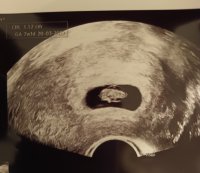

hjertet banket og vi fikk til og med et lite hopp. Målte helt riktig til hvor langt jeg var